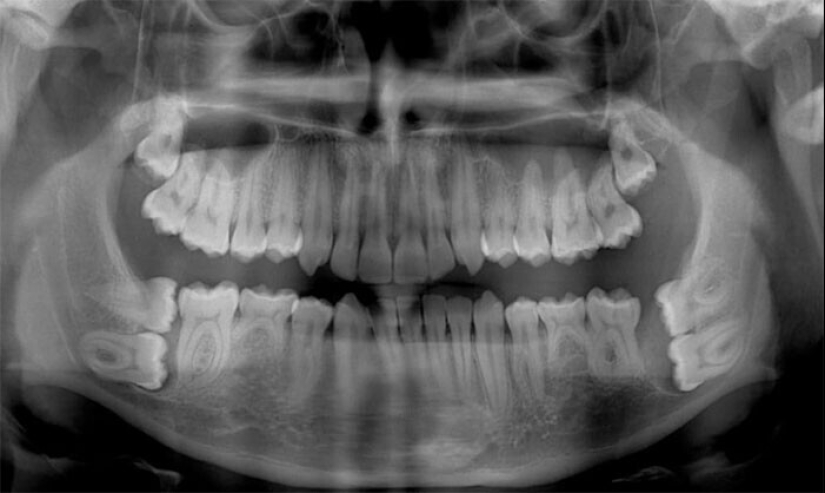

"Soy un dentista, pero los rayos x de los niños de 6-12 años me asustan un poco todavía"